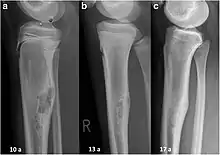

| Non-ossifying fibroma of tibia | |

Over the past two decades, CT guided radiofrequency ablation has emerged as a less invasive alternative to surgical resection in the care of benign bone tumors, most notably osteoid osteomas. In this technique, which can be performed under conscious sedation, a RF probe is introduced into the tumor nidus through a cannulated needle under CT guidance and heat is applied locally to destroy tumor cells. Since the procedure was first introduced for the treatment of osteoid osteomas in the early 1990s,[20] it has been shown in numerous studies to be less invasive and expensive, to result in less bone destruction and to have equivalent safety and efficacy to surgical techniques, with 66 to 96% of patients reporting freedom from symptoms.[21][22][23] While initial success rates with RFA are high, symptom recurrence after RFA treatment has been reported, with some studies demonstrating a recurrence rate similar to that of surgical treatment.[24]